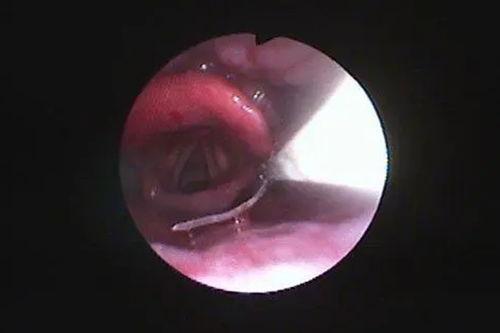

4. 观察:喉镜的镜头会将喉咙内部的情况实时传输到屏幕上,医生可以清晰地看到喉咙、气管等部位的情况。

下面是一段喉镜检查的视频,让我们一起看看这个神奇的过程吧!

[视频:喉镜检查全过程]